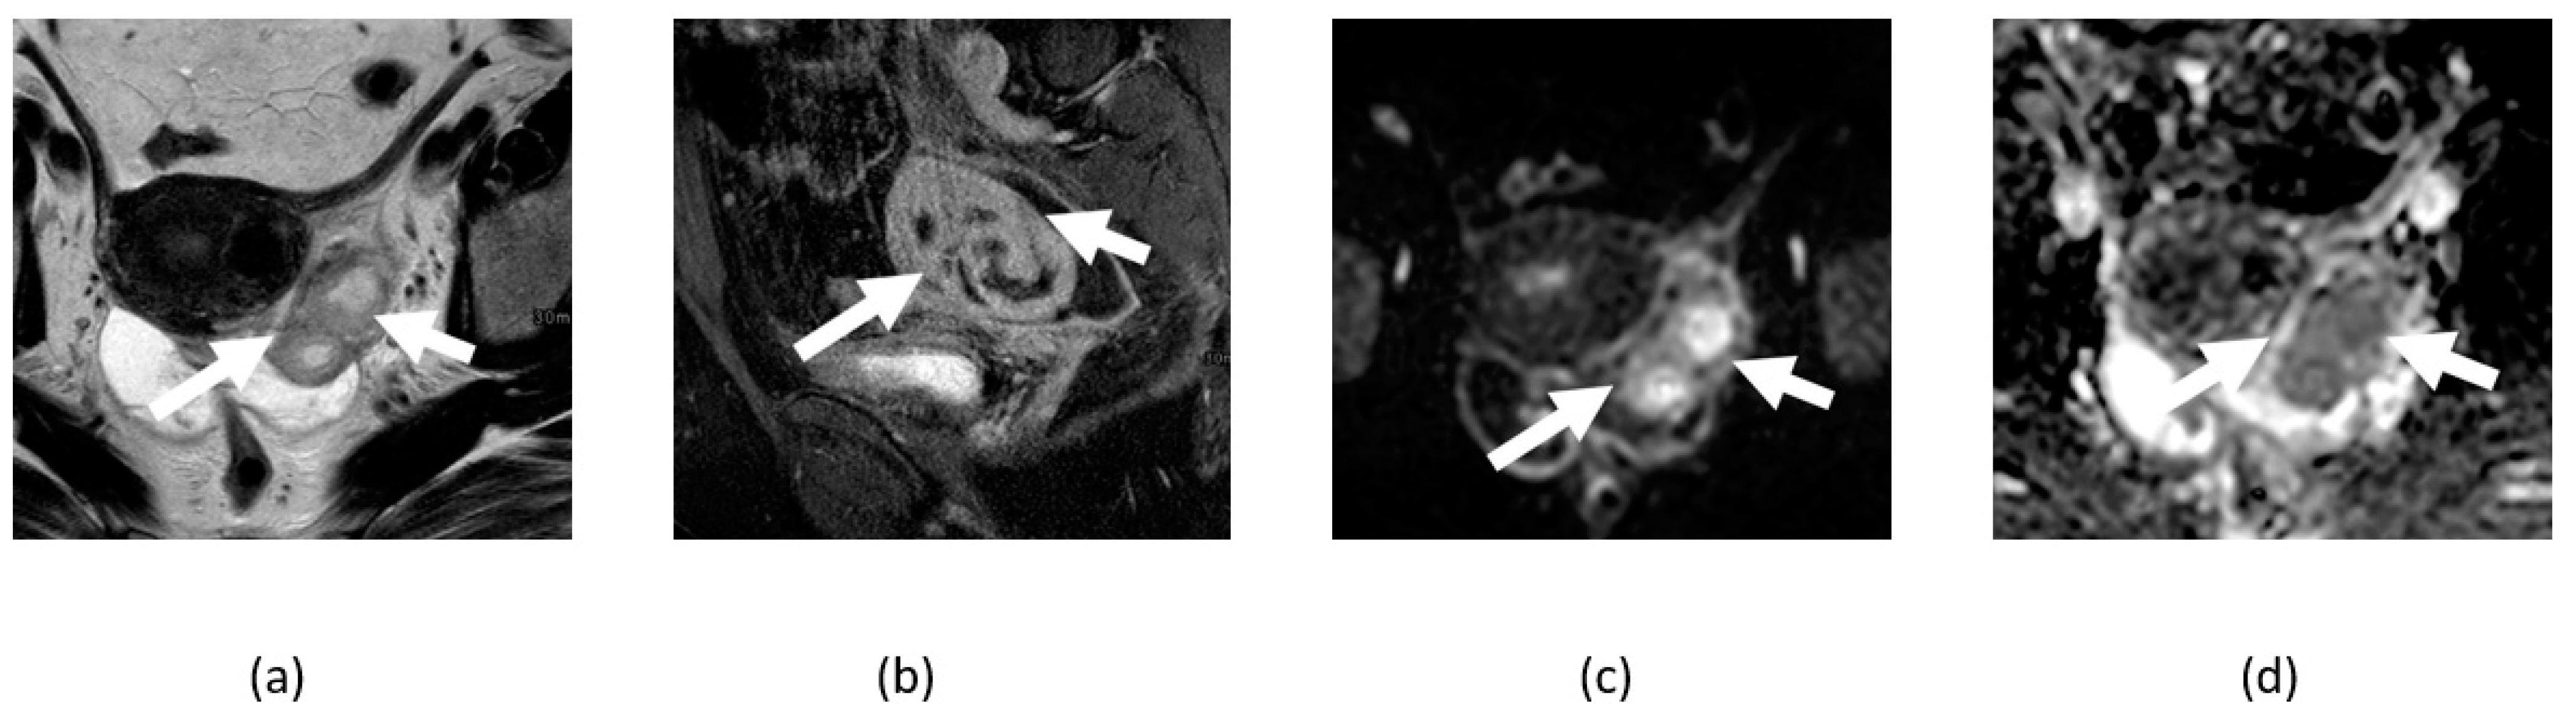

4.3. Ovarian Cancer